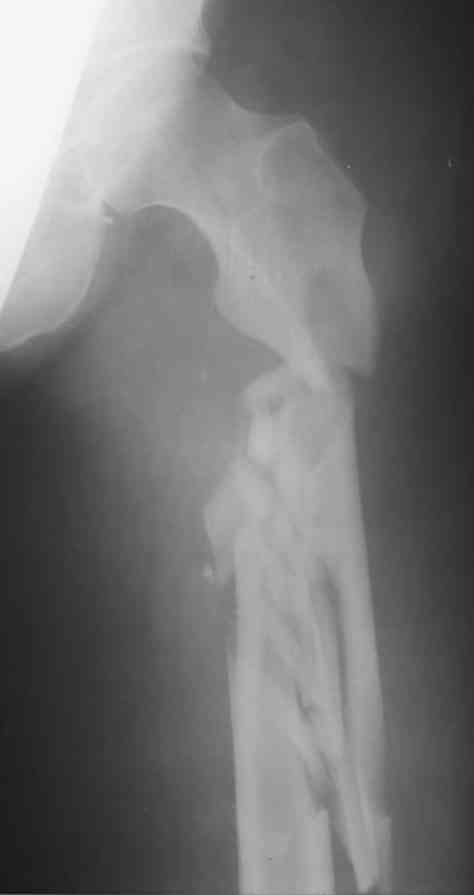

Перелом бедра

Не знаю что делать? Помогите, у кого есть какие мысли по фиксации данного перелома.

приветствую,коллега!хотелось бы увидеть и вторую проекцию , а так же узнать механизм травмы и состояние мягких тканей (+возраст больногго ,его запросы и Ваши возможности). пока по данному снимку перелом можно лечить и вытяжением , и ЗИМО , и АВФ . Что Вам ближе ?

Коллега если есть возможность, то нужно фиксировать или PFN-a или гамма гвоздем удлинненами версиями.Удачи

DCS с длинной ножкой. Успехов !

Очевидно, лучший выход - закрытый интрамедуллярный остеосинтез каким-то из "цефаломедуллярных" гвоздей. Каким именно- это второстепенные нюансы.

Можно PFN, PFNa (длинные). Если нет ЭОПа, то наверное спице-стержневой аппарат подойдет.

Ув. Евгений по всей видимости сопоставление данного перелома будет проблематичное при любом варианте оперативного вмешательства. на мой взгляд единственным рещением есть реконструктивный интрамедулярный стержень. Не старайтесь точно отрепанировать. сохраните питание отломков и выставьте правильную ось бедра это Ваша главная задача. УДАЧИ.